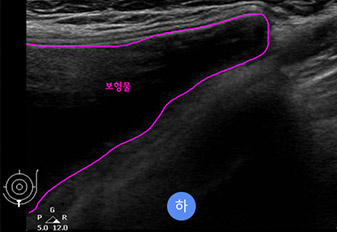

* This is an actual breast ultrasound examination screen after

breast augmentation surgery at View Plastic Surgery. *